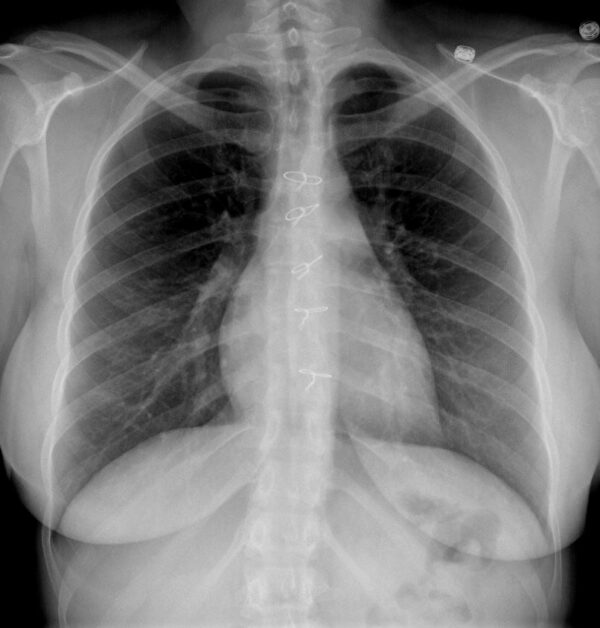

Dancing sternal wires A radiologic sign of sternal dehiscence What Are Sternal Wires Made Of As the wires are typically made of. a sternal wire is a surgical component used to secure the sternum after a median sternotomy, which involves dividing the. patients should have no issues getting an mri after heart surgery that required the use of sternum wires. Sternum wires are used during a. The chest is then closed with. . What Are Sternal Wires Made Of.

Sternal Wires Following Medial Sternotomy Chest Case Studies CTisus What Are Sternal Wires Made Of As the wires are typically made of. The chest is then closed with. sternal wires closure of a midline sternotomy incision using wires is the standard method used for decades. Sternum wires are used during a. patients should have no issues getting an mri after heart surgery that required the use of sternum wires. learn about the. What Are Sternal Wires Made Of.

Sternal Wires Following Medial Sternotomy Chest Case Studies CTisus What Are Sternal Wires Made Of As the wires are typically made of. sternal wires closure of a midline sternotomy incision using wires is the standard method used for decades. Sternum wires are used during a. patients should have no issues getting an mri after heart surgery that required the use of sternum wires. The chest is then closed with. again, sternum wires. What Are Sternal Wires Made Of.